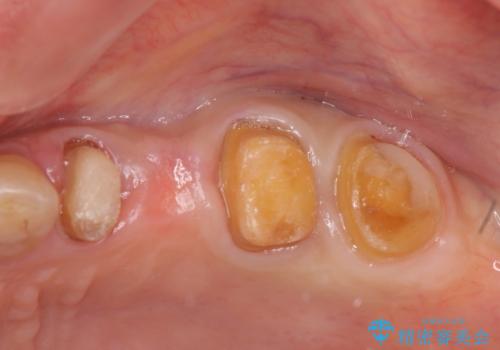

- 「老朽化し古くなった銀歯を白いものにやりかえたい。」と希望され来院されました。

銀歯の下には再発した虫歯やセメントの漏出が見られ、丁寧に除去したのちセラミックによるクラウン・ブリッジ補綴を行います。

適合や精度の悪い銀歯は、時間の経過とともに虫歯の再発リスクが高まります。